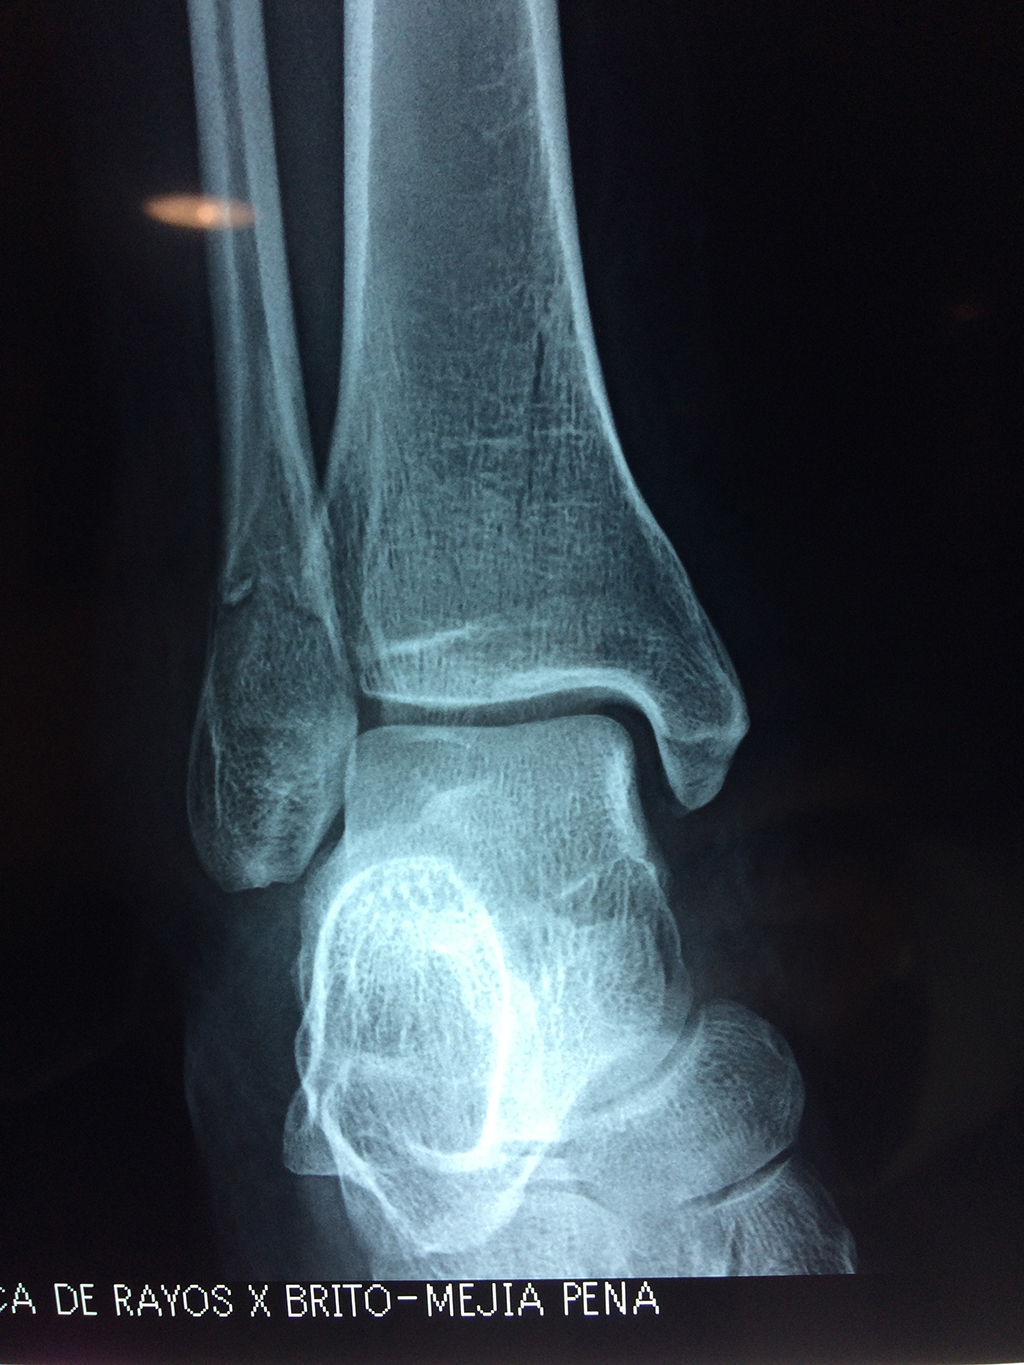

Una fractura de tobillo es la rotura de uno o más de los huesos del tobillo. Estas fracturas pueden ser:

Algunas fracturas de tobillo pueden requerir cirugía si:

- Los extremos de los huesos están desalineados entre sí (desplazados).

- La fractura se extiende hasta la articulación del tobillo (fractura intra-articular).

- Los tendones o ligamentos (tejidos que sujetan los músculos y los huesos entre sí) están rotos.